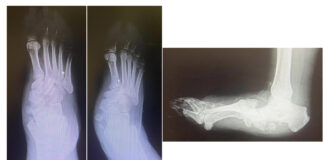

Piede di Charcot, rara complicanza del diabete: al Gemelli soluzioni avanzate